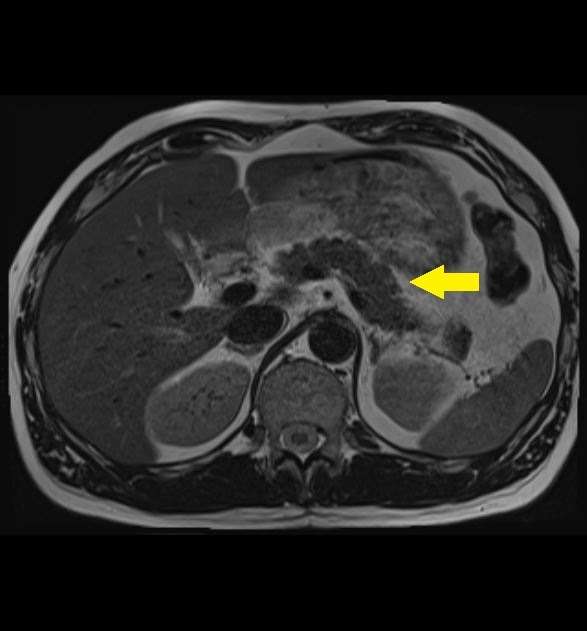

20220914082754.jpg。放射線科|八潮中央総合病院。正常画像と並べてわかる腹部・骨盤部MRI―ここが読影のポイント。対象検査部位・撮像手法|UNB住吉神社前クリニック 放射線科。「腹部のMRI」荒木 力定価: ¥ 13000#荒木力 #荒木_力 #本